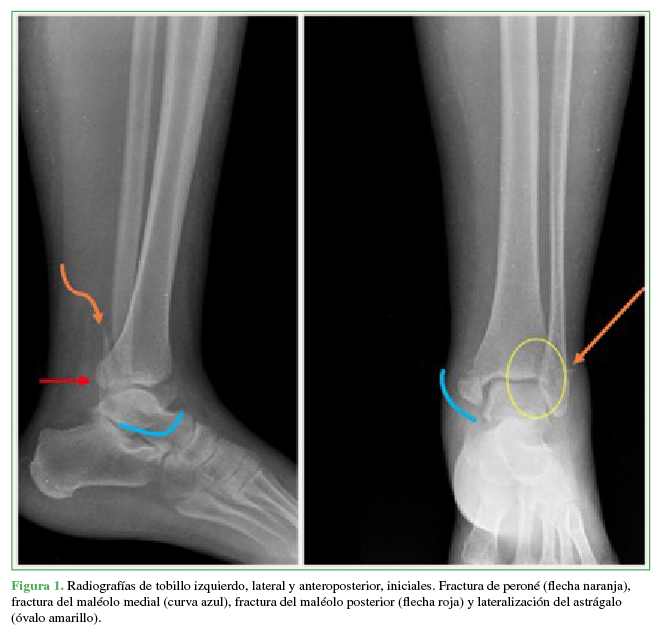

La paciente ingresó con radiografías simples anteroposterior y lateral del tobillo izquierdo que mostraban una fractura trimaleolar con traslación lateral del astrágalo (Figura 1). Luego de analizar las imágenes, se diagnosticó luxofractura trimaleolar del tobillo izquierdo. Se procedió a la reducción cerrada con sedación farmacológica a cargo del Servicio de Medicina de Urgencias. Se la inmovilizó con una férula posterior.

Después del procedimiento, no hubo cambios en el examen físico neurológico o vascular de la extremidad y se solicitó una tomografía computarizada simple del tobillo derecho para caracterizar las lesiones y para la planificación quirúrgica. En las imágenes de control, se observó el compromiso trimaleolar ya descrito con componente adicional en la región anteromedial y distal del peroné que correspondía a una fractura del proceso de Wagstaffe-Le Fort (Figura 2); por lo tanto, se decidió considerar el cuadro como un equivalente cuadrimaleolar. Se procedió a la osteosíntesis y reconstrucción ligamentaria de forma ambulatoria y se le dio de alta con analgésicos y recomendaciones para disminuir el edema.